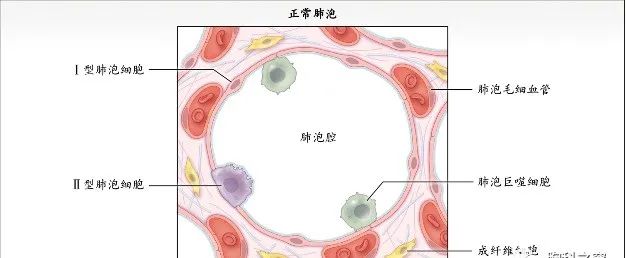

病理生理学

机化性肺炎的发病机制尚不清楚。从病理角度看,肺组织结构似乎未发生严重破坏。

COP是炎性和纤维增生过程,以肺泡内纤维增生为特征,经过免疫抑制或抗炎治疗后可逆(有时不可逆)。

COP患者肺活检标本的组织病理学结果显示腔内有疏松结缔组织栓子,累及肺泡腔和肺泡管,也可累及细支气管,肺的基础结构保留。腔内疏松结缔组织栓子常以细柄连接到肺泡壁,并通过肺泡孔从一个肺泡延伸到相邻的肺泡,形成特征性的蝴蝶状结构。肺泡壁可出现轻度慢性炎症(如涉及淋巴细胞和浆细胞)。

COP的主要病理变化是肺泡内、肺泡管、呼吸性细支气管及终末细支气管内有息肉状肉芽组织增生,形成Masson小体,其病变表现单一,时相一致,呈斑片状和支气管周围分布,位于气腔内,含极少炎性细胞,肺结构往往正常。肺泡腔内肉芽组织呈芽生状,由疏松的结缔组织将成纤维细胞包埋而构成,可通过肺泡孔从一个肺泡扩展到邻近的肺泡,形成典型的“蝴蝶影”。肉芽组织中可存在炎性细胞,尤其在疾病早期,可见单核细胞、巨噬细胞及少量的肥大细胞、嗜酸粒细胞、中性粒细胞。在空的肺泡腔内可见肺泡巨噬细胞,部分肺泡巨噬细胞呈泡沫状,伴有Ⅱ型肺泡上皮细胞增生。受累的肺泡间隔有少量淋巴细胞和浆细胞浸润为主的轻度炎性渗出,肺泡间隔稍增厚。